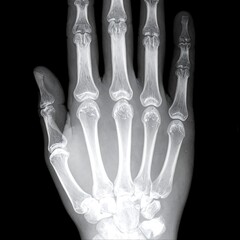

Podobny obraz Medical Elbow Anterior View X-Ray Radiograph Illustrating...